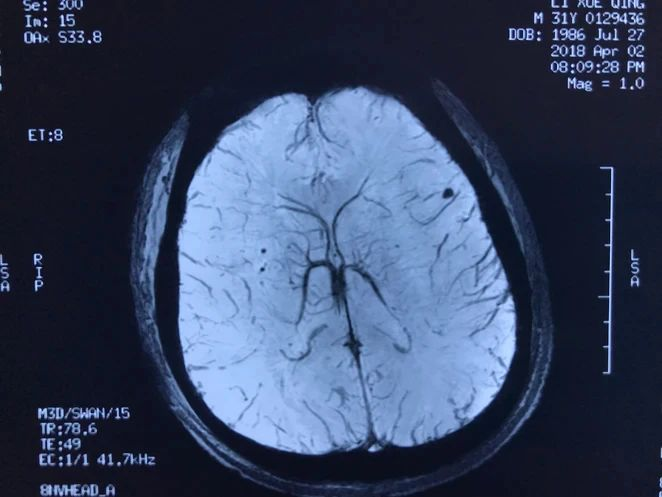

病人多发脑海绵状血管畸形,本次出血部位位于桥脑。第一次出血,术前偏瘫,转入我病房时为出血一月左右,采取颞下岩前入路切除脑干病变,术后病人肢体肌力较术前有提高,目前尚未出院。

本次手术资料:

术后磁共振显示脑干病变消失